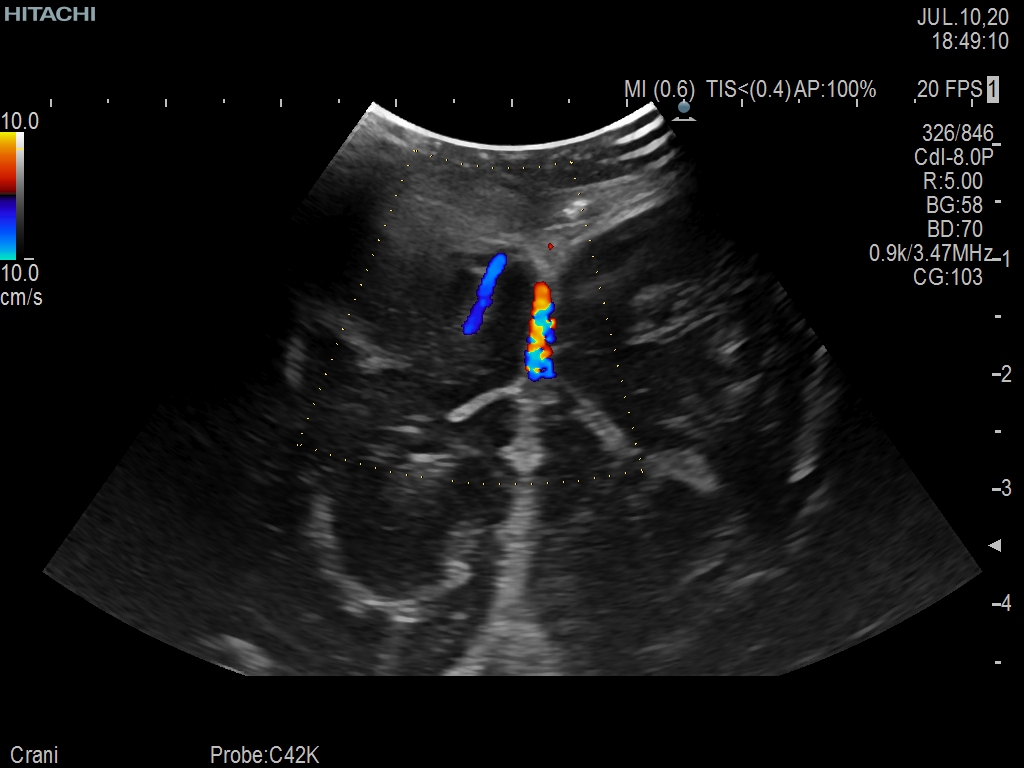

Superior guidance for all applications

Fujifilm Healthcare Americas is committed to designing tools that help surgeons navigate inside the human body and provide the necessary information to immediately make critical surgical decisions.

Fujifilm Healthcare's dedication to Surgeons provides outstanding ultrasound technology, professional support and the specialized tools necessary to best perform comprehensive real-time ultrasound imaging in Breast Surgery, General Surgery, Laparoscopic Surgery, Neurosurgery, Robotic Surgery and Surgical Oncology.

Recognized for our outstanding image quality, outstanding system reliability and intuitive use of cutting edge technology, Fujifilm Healthcare remains the standard in the field of Surgery.

Recognized for our outstanding image quality, outstanding system reliability and intuitive use of cutting edge technology, Fujifilm Healthcare remains the standard in the field of Surgery.

A critical function of robotic ultrasound guidance is tumor margin identification. Fujifilm's family of robotic probes all have the optimum location of the attaching mechanism that allows for full wrist articulation of the probe. The result is an increased confidence that the tumor margins have been completely identified.